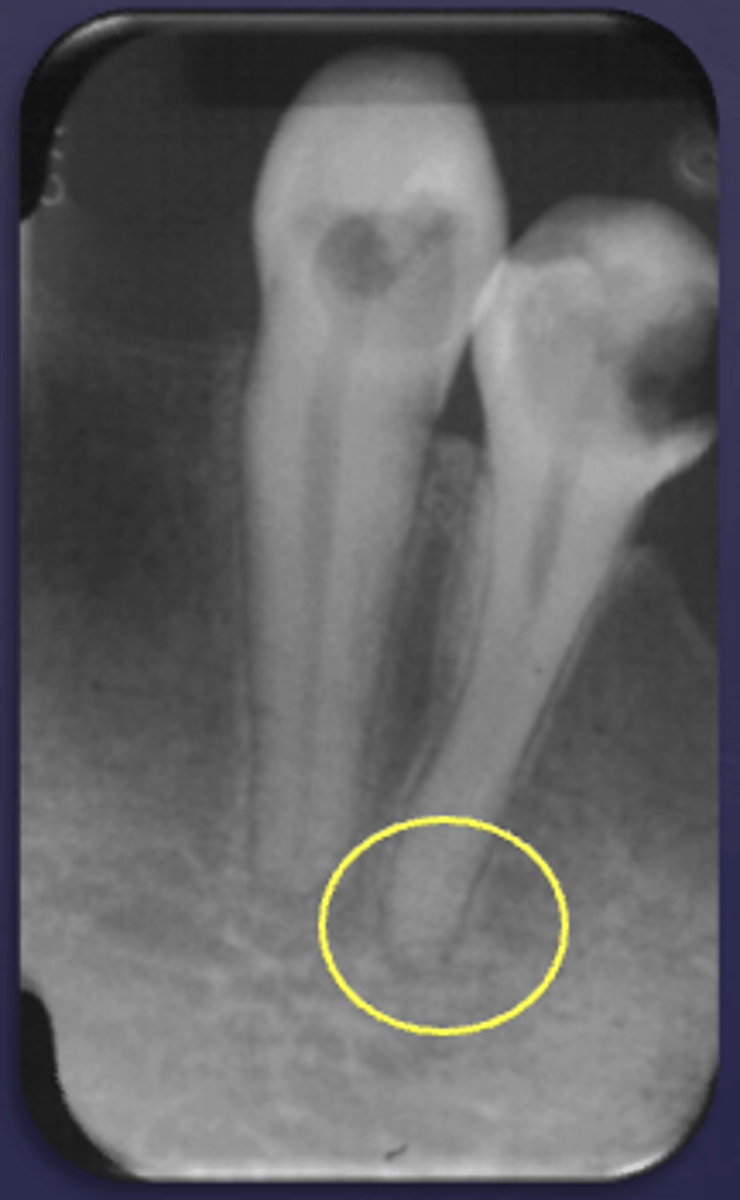

What type of change is seen in this radiograph?

early change (apical periodontitis #30)